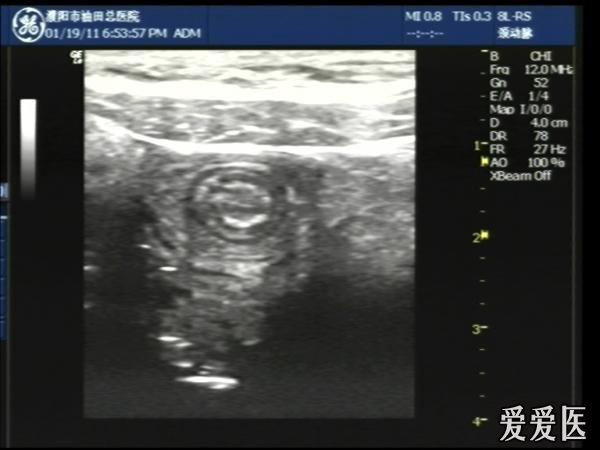

超声检查:于下腹部可见“双环征象”,双环重叠长约6mm,检查期间观察可见肠蠕动;CDFI:未见明显异常血流信号。

超声提示:下腹部双环征,考虑肠套叠可能,请结合临床

“套筒征”、“同心圆征”,很清晰,很经典!

好图,同心圆征。清晰